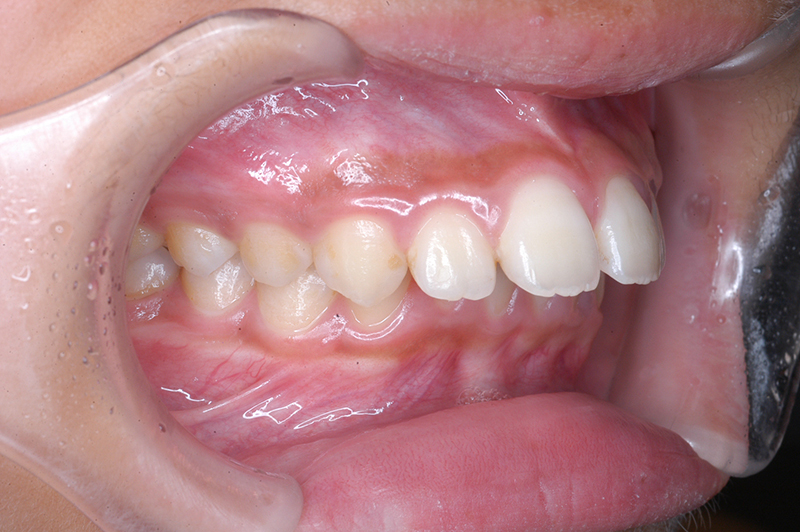

動的治療終了時

FP・IOP

批評・予后 上顎前歯舌側移動により上口唇形態は改善したこと、また動的治療中の下顎骨、特に下顎枝の成長が認められ下顔面高さは高くなったことが相俟って良好なプロファイルは得られたと思う。咬合の緊密化や歯根のパラレリングは行えたように思う。今後は第三大臼歯の萌出方向に注意を払い、頃合いを見計らって抜歯を検討している。